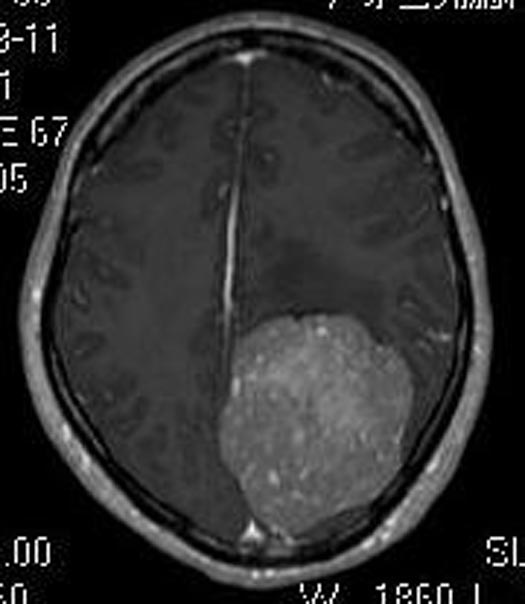

吴小姐4个月前出现反复头痛,伴有双眼视物模糊,偶有右耳耳鸣,无明显头痛等不适,当地医院头颅CT检查提示“左侧顶枕叶占位,考虑脑膜瘤”;广东三九脑科医院头颅MR检查显示:左侧顶枕部占位性病变,范围约7.1cm×6.8cm×5.9cm;进一步行头颅CTA检查提示:其内血供丰富。

由鲁明主任主刀,在全麻下行左侧顶枕部巨大脑膜瘤切除术,术中见肿瘤呈灰褐色,质中,边界较清,血供丰富,显微镜下分块全切肿瘤,手术过程顺利。术后吴女士头痛症状明显较前好转,四肢肌力、肌张力正常,康复出院。术后病理结果提示:脑膜皮细胞型脑膜瘤 WHO I级。